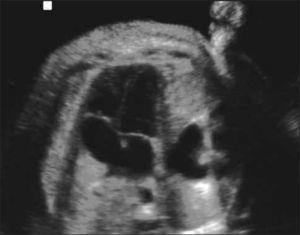

Hernia diafragmática (HDC). Se presenta con frecuencia de 1 en 4000-10.000 embarazos. Se relaciona en un 30% con defectos anatómicos y alteraciones cromosómicas. Esta malformación se produce por defecto a nivel del diafragma y la herniación de parte del contenido abdominal hacia el tórax. El diagnóstico es difícil y en la mayoría de los fetos no se diagnostica en primer trimestre ya sea porque el defecto es pequeño o porque las vísceras abdominales aún no se han herniado por el defecto diafragmático (Figura 6).